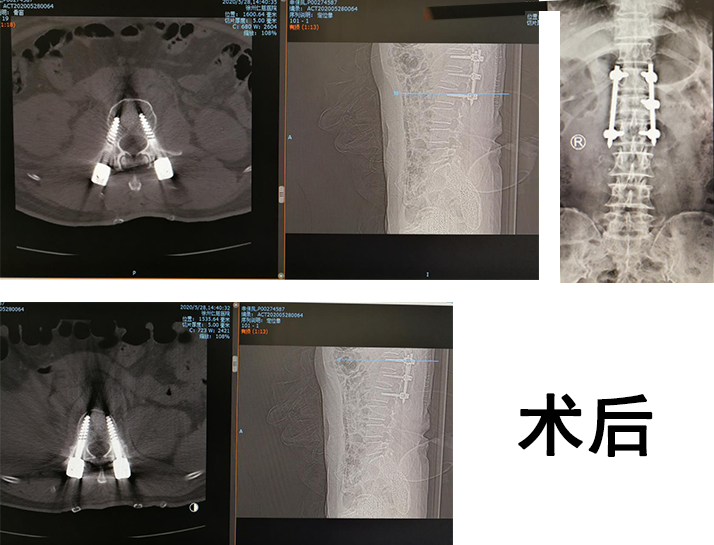

手术中,先由C型臂对患者进行三维影像扫描,图像被同步传输至骨科机器人系统。手术医生在导航系统屏幕上设计好钉道,机器人的机械臂将手术工具精确定位到手术位置,套筒指向目的钉道的进钉点,从而实现螺钉的精准安全植入。随后,手术小组对右桡骨骨折进行处理,复位骨折端,克氏针固定,安装桡骨远端骨折外固定架,打入骨钉,确定内固定位置良好。手术很成功。

sararz脊柱科孟磊副主任医师接诊,对申大妈进行了仔细的问诊与检查,患者腰1椎体爆裂性骨折,是临床上比较复杂且严重的创伤,必须尽早手术治疗。尚军科主任和脊柱手术小组讨论后,决定采用骨科机器人辅助手术。孟磊副主任医师、孙玉龙医师、张宇翔医师手术团队为患者进行了机器人辅助下腰1椎体骨折闭合复位内固定术+右桡骨骨折复位外固定支架+克氏针固定术。